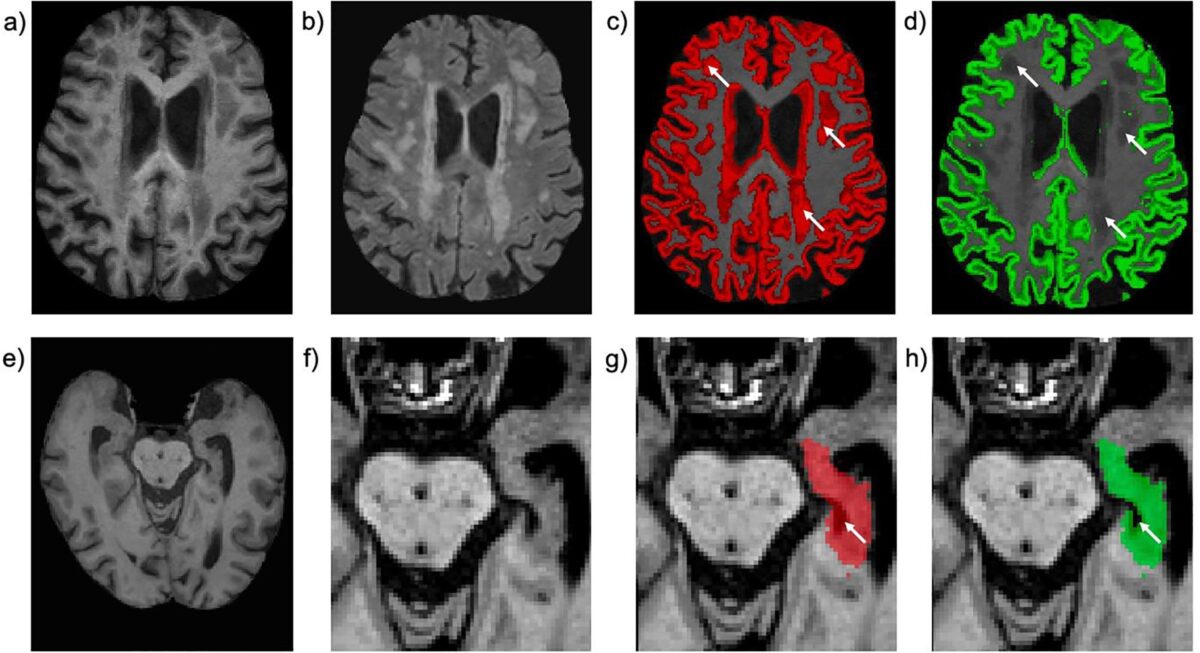

هر داوطلب در ابتدا اطلاعاتی از سبک زندگی خود و نمونه خون ارائه داد. سپس در مرحله تصویربرداری، طی ملاقاتهای پنجساعته، بیش از ۱۲ هزار تصویر MRI از مغز، قلب و شکم آنها ثبت شد. همچنین اسکنهایی برای سنجش تراکم استخوان و چربی بدن و سونوگرافی از شریانهای کاروتید انجام گرفت.

پروفسور لوئیس توماس، استاد تصویربرداری متابولیک دانشگاه وستمینستر گفت: «اکنون پژوهشگران میتوانند اندازه، شکل و ترکیب هر عضو و بافت بدن را در چند ثانیه اندازهگیری کنند. این کار قبلاً ساعتها زمان میبرد.»